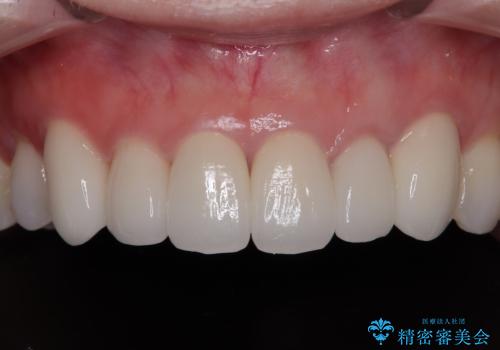

矯正治療自体はインビザラインで満足のいく仕上がりとなりました。

前歯は根管治療が必要となり、元々舌側に入り込んでいた左上2番目の歯は歯周外科処置により歯肉ラインを整えることとしました。

欠損部位は傾斜歯軸を起き上がらせることができたため、オールセラミッククブリッジにて補綴治療を行いました。

全顎的に満足のいく仕上がりとなりました。